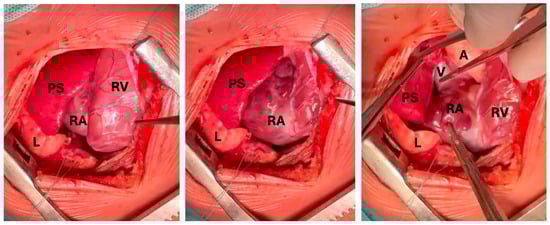

Intrapericardial Extralobar Pulmonary Sequestration: A Case Report and Systematic Review of a Unique Embryologic Variant

Background: Intrapericardial extralobar pulmonary sequestration (ELPS) is an exceptionally rare congenital malformation. The location may mimic neoplastic lesions and poses diagnostic and surgical challenges. We present a new case and a systematic review of the literature. Case Presentation: A 3-month-old male infant was referred for evaluation of a congenital intrathoracic mass suspected to be an extralobar sequestration. However, intrapericardial location was not recognized. MRI and CT demonstrated a circumscribed lesion with arterial supply from the right pulmonary artery. Thoracoscopic exploration was attempted but converted to sternotomy. The mass was excised en bloc. Histopathological analysis confirmed extralobar pulmonary sequestration with cystic components, consistent with a hybrid lesion. Postoperative recovery was uneventful. Methods: A systematic literature review was conducted according to PRISMA guidelines across PubMed, Scopus and Embase databases, including only histologically confirmed intrapericardial ELPS. Results: Ten cases were identified. Including the present case, eleven cases have been reported. Prenatal detection occurred in 54% of cases. Fetal demise occurred in two cases due to cardiac tamponade. Aberrant arterial supply originated from the pulmonary arteries in 54% of patients and venous drainage into the right atrium or superior vena cava in 45%. Surgery via sternotomy was performed in all cases with excellent outcomes. Conclusions: Intrapericardial ELPS is an exceptionally rare but surgically curable entity. Early recognition and complete resection are essential to prevent life-threatening complications. This systematic review highlights a consistent vascular pattern supporting its classification as a unique embryologic variant within the CPAM–sequestration spectrum. Full article

Figure 1